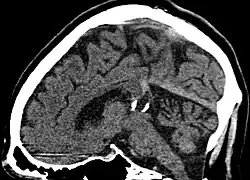

| Calcified cyst of pineal gland in CT. Sagittal MPR. |